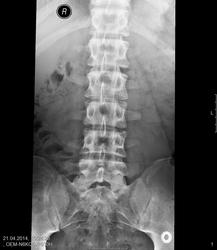

Указанное стрелочками - грыжи Шморля? Пациент 19 лет, ДДЗП.

Да. Еще я бы отметил грыжу Шморля в L2 по нижней замыкательной пластинке и L3 по верхней замыкательной пластинке.